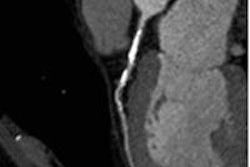

Image of CORE320 patient shows an occluded left anterior descending (LAD) stent on CT and catheterization, with the corresponding anterior wall defect demonstrated by CT perfusion and SPECT. Image courtesy of CORE320 investigators.The value of CT perfusion

Both invasive coronary angiography and CTA provide morphologic data, but they lack the physiologic information needed to determine the hemodynamic significance of a lesion. Proving that functional significance requires either catheter-based fractional flow reserve techniques, or noninvasive modalities such as SPECT myocardial perfusion imaging (MPI), PET, or MRI, the authors explained (Eur Heart J, November 19, 2013).